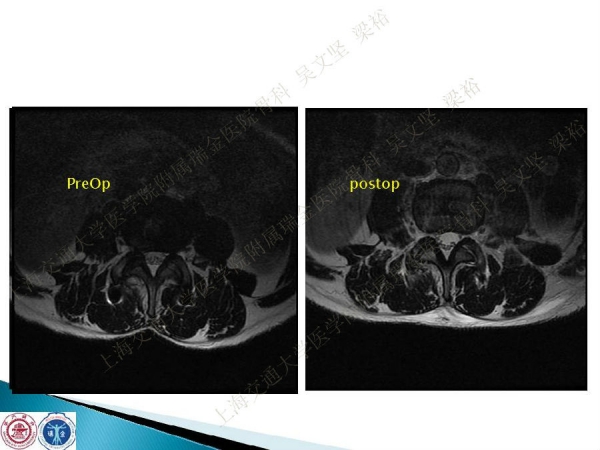

腰椎融合术后临近节段发生的退行性病变(adjacent segment disease,ASD))是一种常见的并发症。ASD的发病率相当高,而且涉及的范围很广。传统翻修手术治疗ASD有软组织剥离多、出血多、术后康复时间较长以及引起新的并发症的风险。本文结合病例介绍了运用Stand alone DLIF技术治疗ASD的方法与其优势。